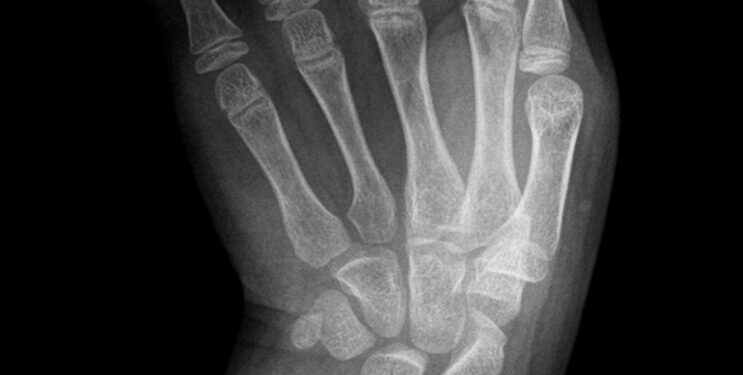

Kaip nustatoma ši liga

Diagnozuoti dažniausiai padeda išsamus gydytojo apžiūra ir ligos istorija. Kaulų būklei vertinti taikomi rentgenologiniai, kompiuterinės tomografijos tyrimai. Kartais atliekami būtini tyrimai – paimami audinių ar kaulo mėginiai ištyrimui mikroskopu.